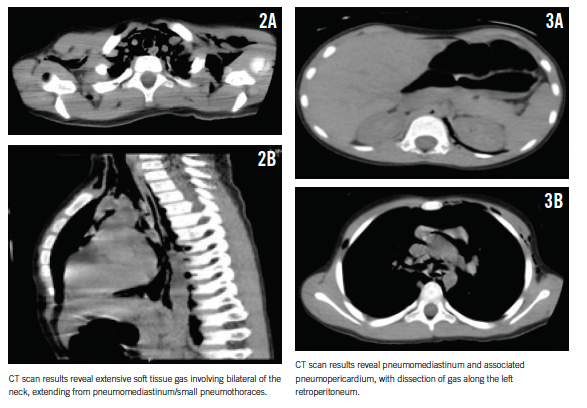

On auscultation over the chest, a systolic crunching sound was heard, with accentuation during inspiration (Hamman sign). The rest of the boy’s physical examination results were unremarkable. However, a bedside chest radiograph revealed pneumomediastinum (Figures 1A and 1B).

For better delineation of the extent of air dissection, a computed tomography (CT) scan of the chest was obtained, which revealed extensive pneumomediastinum, small bilateral pneumothoraces, pneumopericardium, and pneumoretroperitoneum mostly on the left (Figures 2 and 3).